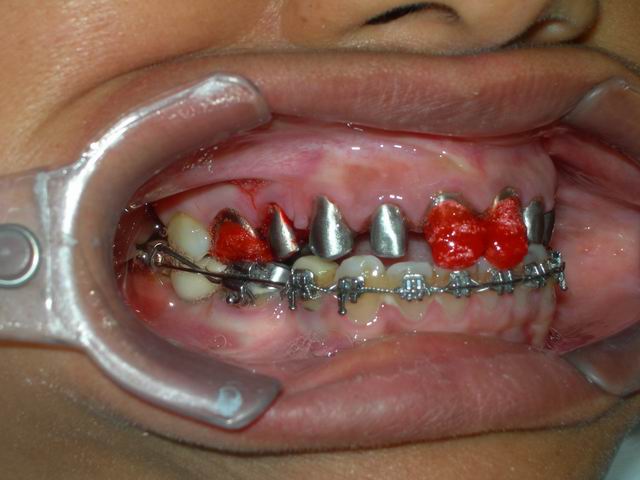

Início da fase reabilitadora, após conclusão do alinhamento e nivelamento ortodôntico: preparo inicial para confecção de núcleos metálicos em dentes naturais desvitalizados (tratados endodonticamente)

Arcada superior preparada e arco inferior com aparelho ortodôntio instalado, com a funcão de contenção enquanto aguarda o momento da intervenção reabilitadora